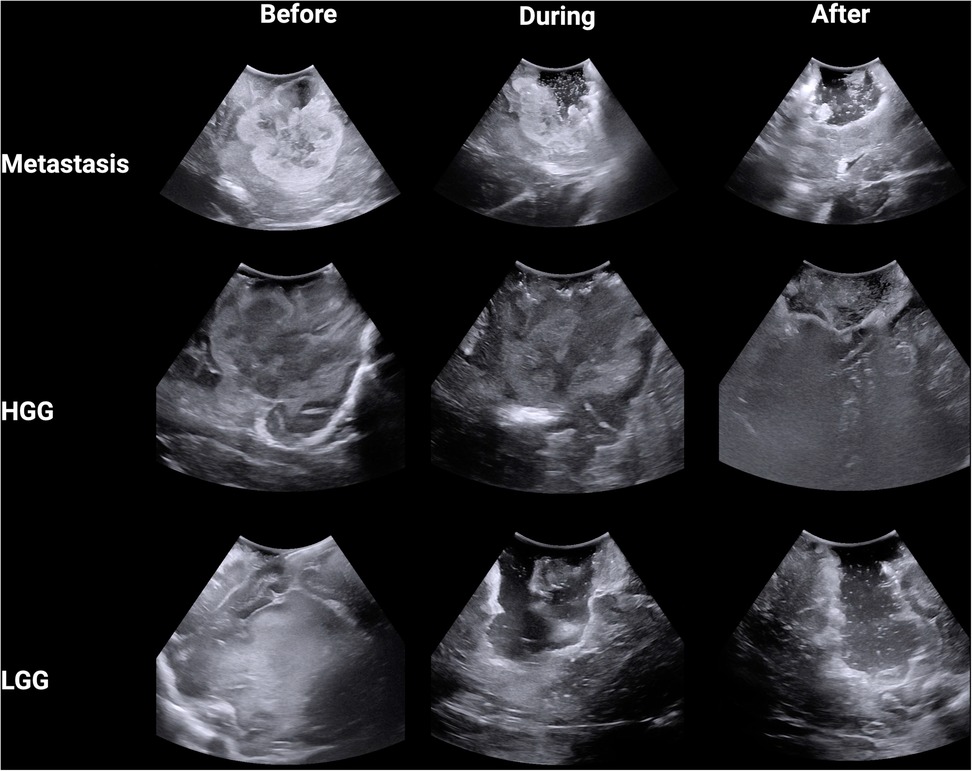

A total of nine anonymized representative iUS images were captured from three procedures (Figure 1). The GE healthcare bk5000 ultrasound device was utilized. The iUS images were optimised by the operating surgeon (NB) across 3 parameters: frequency (5–13 MHz), depth (10–80 mm) and gain. The images included a histologically confirmed high grade glioma (HGG), low grade glioma (LGG) and brain metastasis. We chose the commonest intra-axial tumours treated surgically in our department with a known span of margin ambiguity. During each procedure, images were captured at three stages: before tumour resection, during resection and near completion of resection. A total of 18 neurosurgeons participated in the study. First, participants completed a survey detailing their grade (attending, fellow or resident) and their experience with using intra-operative ultrasonography for brain tumour surgery (<10 cases; 10–25 cases; 25–50 cases or >50 cases). Using 3D Slicer, participants were invited to draw around (segment) what they believed was tumour in the nine images. Participants were supported with the use of 3D Slicer by members of the research team (AJ, JW, OS). Participants were free to decide how many areas to segment, including none. For each image, the participant also rated how difficult they found the segmentation on a Likert scale from 1 (very easy) to 10 (very hard). Ethical approval was waived for this study as it used anonymised images captured as part of routine practice and involved voluntary participation by neurosurgeons.

Figure 1. Intra-operative B-mode ultrasound images from three tumour types across three stages of surgery.

A total of 18 neurosurgeons participated in the study including 5 attendings, 7 fellows and 6 residents. From this group, a total of 1,377 DSCs were calculated across the 9 iUS images. Metastasis had the highest DSC (0.72 ± 0.32), followed by HGG (0.64 ± 0.33) and then LGG (0.58 ± 0.25; p < 0.00001) (Figure 2A). As the resection progressed, the degree of inter-observer agreement broke down. Before resection the DSC was 0.871 ± 0.105; during resection (0.74 ± 0.174) and at completion (0.32 ± 0.270; p < 0.00001) (Figure 2B). Observers reported increasing difficulty with iUS interpretation as the resection proceeded and there was statistically significant (p = 0.014) negative correlation (−0.775) between DSC and difficulty rating of the segmentation (Figure 2C). The trend of decreasing agreement as the resection progressed held across tumour types. It was most pronounced in HGG where there was a near complete breakdown of agreement in the resection cavity (0.26 ± 0.28) (Figure 3). Heats maps for the iUS demonstrated the spatial variation in observer agreement across the tumour types and stages of surgery (Figure 4). It shows decreasing agreement as the resection proceeds particularly within the margins of the resection cavity near the end of the resection. From the 18 participants, there were 5 observes who were highly experienced with iUS (>50 cases) and 6 observers with low experience (<10 cases). There was no significant difference in DSCs between the high and low experience observers across the tumour types and stages of surgery.